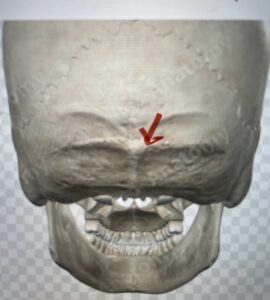

Although some patients do not require a decompression and just require an occipital cervical fusion, most require some sort of decompression of the neural elements. After a decompression an instrumented fusion is performed. A useful anatomic structure for anchoring the top portion of the construct to the skull is the midline keel of the subocciput. This structure extends from the external occipital protuberance, which corresponds to the confluence of the sagittal and transverse sinuses, to just above the foramen magnum:

(Fig. 1). This bone is quite thick, about 15 mm (Figs. 2a and b). Most modern plate systems utilize three midline keel screws with the option to place within a 2 cm lateral fixation point. This plate is connected to sometimes tricky-to-bend rods and connected to screw fixation points in the cervical spine (Fig. 3). Bone graft material extends from skull to cervical spine.

Fig. 1: Diagram of occipital bone to foramen magnum. Note external occipital protuberance (red arrow)